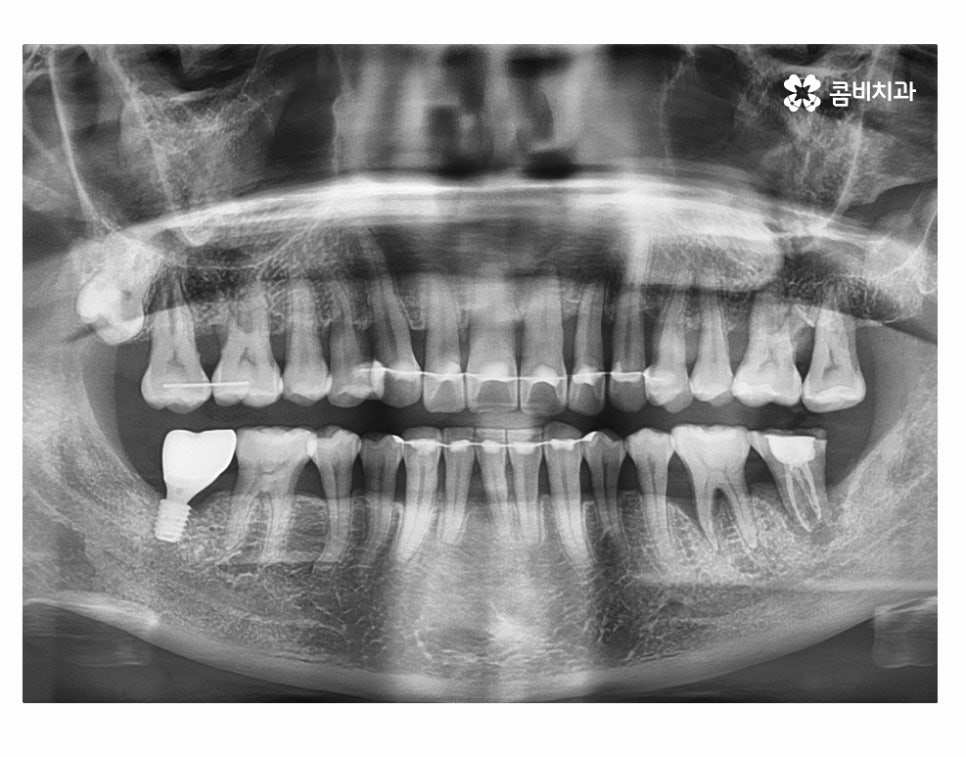

오늘 소개드릴 환자분의 케이스는 치아 상실의 요인이

잇몸질환이 심해져서 치아 뿌리까지 염증이 발생되었고

결국 어금니 발치 까지 이어진 사례라고 할 수 있는데요.

사진에서 보시는 것처럼 치아 사이에 빈 공간도 많고

잇몸이 내려앉아서 치아의 하단부도 많이 드러난 상태인데

치아를 잇몸이 제대로 감싸주지 못하고 이렇게

내려앉게 될 경우 치아도 많이 시리게 되고

치주염이 심해지는 단계에서는 치아가 흔들려서

식사도 제대로 하지 못할 정도로 어려움을 겪게 되실 수 있어요.